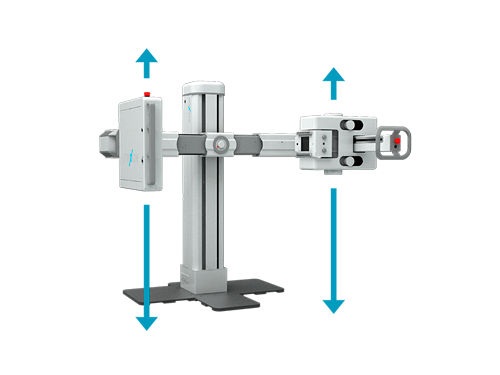

Posiciones y Funciones de Escaneo Versátiles

Ángulo de Rotación de 270°

Cómodo Rango de Movimiento

Movimiento Vertical

Posicionamiento de Cámara

Brazo Recto Extensible

Escaneo Rápido